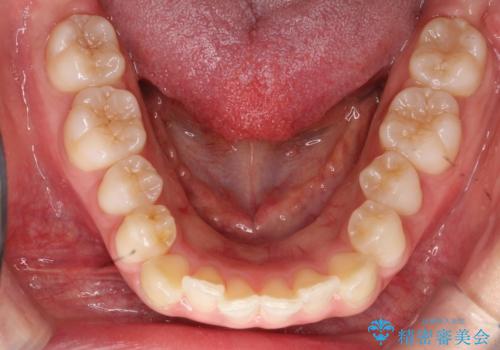

- 口元をさげたいという主訴で来院されました。4番の歯を4本抜歯し、審美装置にて治療をしました。

抜歯をしたことで口元の突出感が改善しました。約2年を予定していた矯正ですが、約1年という短い期間で終了できました。